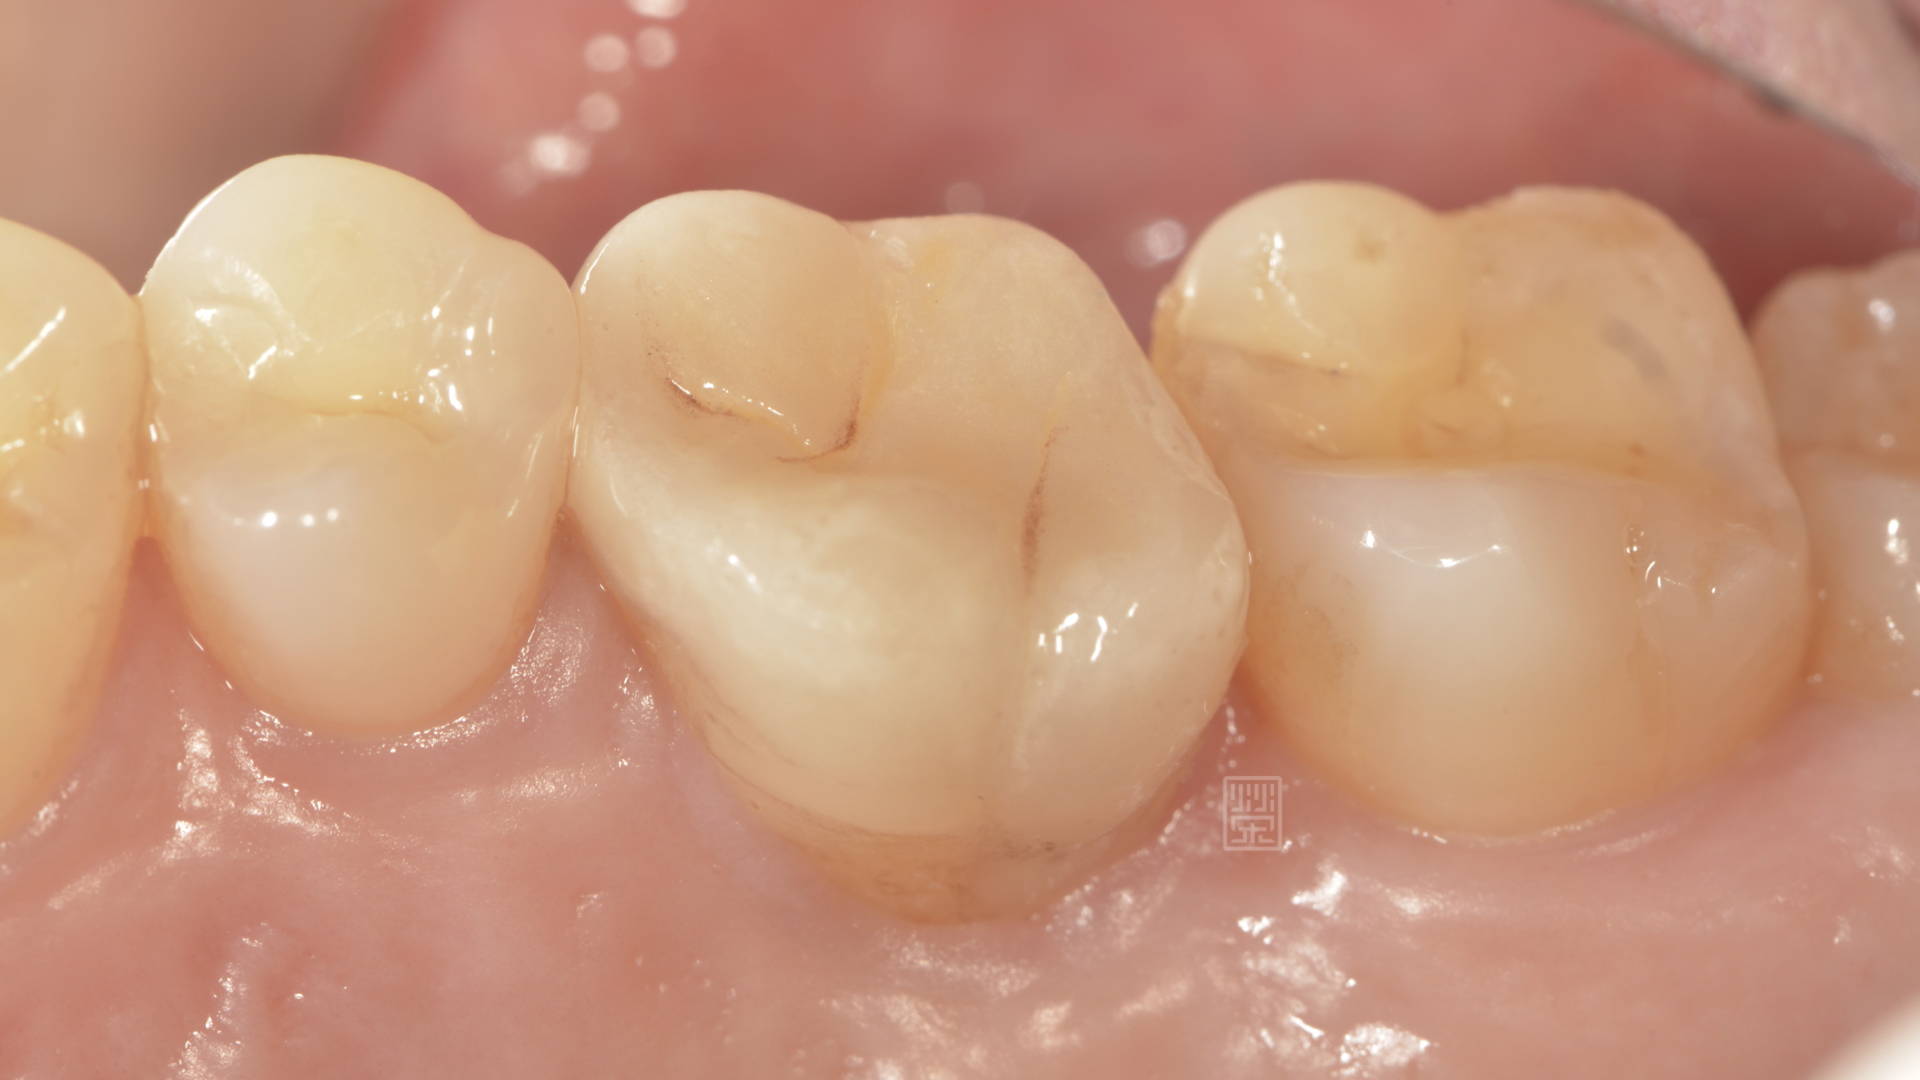

全瓷嵌體完成